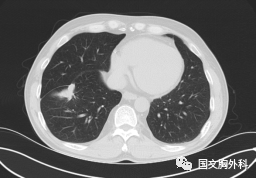

這個(gè)病人檢查胸部CT如圖3:根據(jù)影像學(xué)考慮是惡性腫瘤,行手術(shù)治療后病理回報(bào):“肺膿腫,合并炎癥纖維組織增生”,因此“肺占位”不代表就是惡性腫瘤,診斷金標(biāo)準(zhǔn)是病理診斷。如果檢查后發(fā)現(xiàn)“肺占位”先不要驚慌,及時(shí)就診請??漆t(yī)生會(huì)診指導(dǎo)治療才是關(guān)鍵。